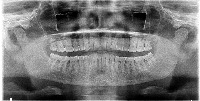

Dental Treatment Planning: The Dentistry computer vision model can be used by dentists and orthodontists for analyzing dental X-rays to identify teeth numbers and conditions like implant, root canal, or crown. By having automatic classification, it will improve the efficiency and accuracy of the treatment planning process.

Dental Education and Training: The model can be utilized as a learning tool for dental students, helping them to familiarize themselves with tooth numbering, implants, crowns, and root canals. This could be implemented in virtual classrooms or integrated into educational mobile applications.

Dental Insurance Claim Processing: The Dentistry computer vision model can be employed by insurance companies to automatically process dental claims. The model can identify the specific treatments or procedures (such as root canals or implants) from the dental X-ray images, leading to faster and more accurate claim processing.

Dental Record Management: Clinics and hospitals can use the Dentistry model to streamline their dental patients' record management by automatically categorizing X-ray images based on tooth number and treatment type. This will help in better organization of patient records and ease of access for future reference.

Dental Research and Analytics: The model can be valuable for dental researchers in the field of oral health analytics. By analyzing large datasets of dental X-ray images, the model can help identify patterns and trends for different treatments and tooth conditions, providing valuable insights for better oral care and health.